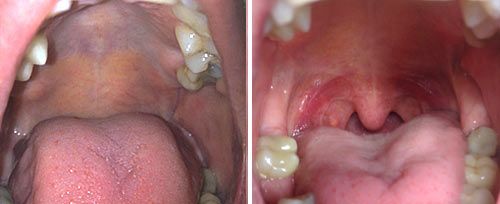

Fotona’s NightLase® therapy is a non-invasive, patient-friendly laser treatment for increasing the quality of a patient’s sleep. NightLase reduces the effects of sleep apnea and decreases the amplitude of snoring by means of a gentle, laser-induced tightening effect caused by the contraction of collagen in the oral mucosa tissue.

Outpatient Erbium:YAG (2940 nm) Laser Treatment for Snoring: A Prospective Study on 40 Patients. Fini Storchi I, Parker S, Bovis F, Benedicenti S, Amaroli A. Lasers Med Sci. 2018;33(2):399-406. doi:10.1007/s10103-018-2436-6. Read Full Text.

Minimally invasive erbium laser treatment for selected snorers. Frelich H, Scierski W, Markow M, Frelich J, Frelich H, Maciej M. Lasers. Med Sci. 2019;34(7):1413-1420. doi:10.1007/s10103-019-02731-6. Read Full Text.